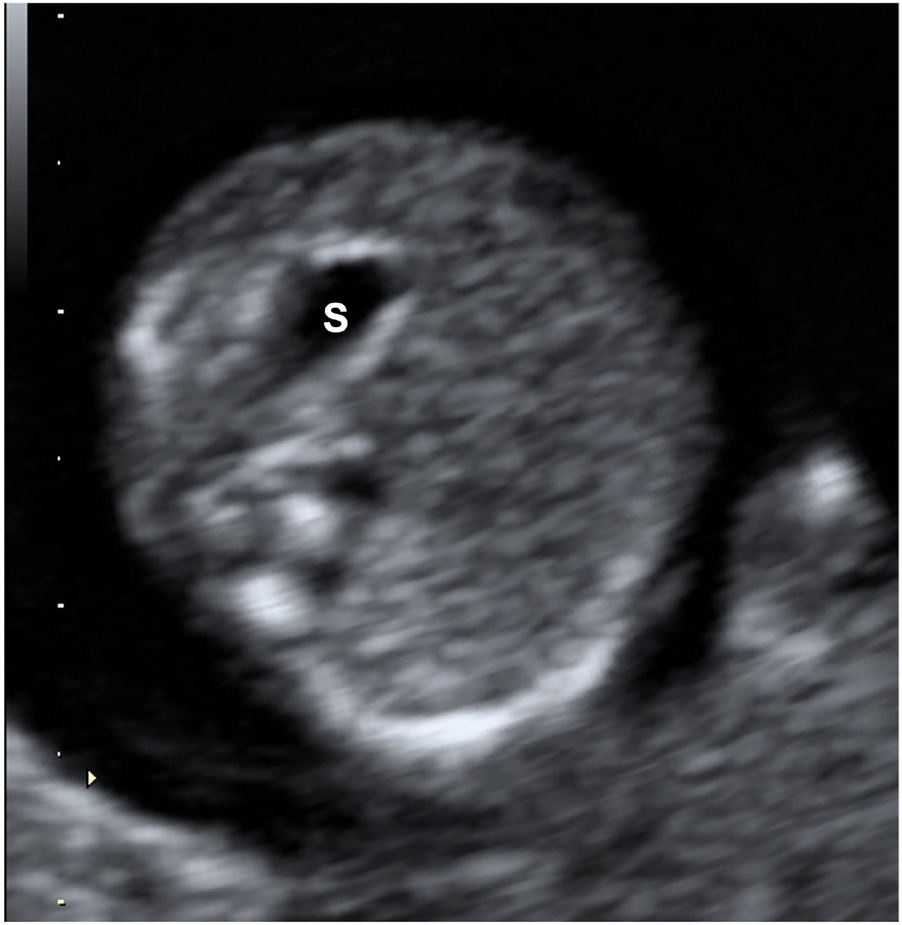

Axial view of the fetal abdomen and stomach (S), lying on the upper left part of the abdomen.

The bladder appears as an anechoic structure in the middle of the fetal pelvis, surrounded by the two umbilical arteries on both sides on axial view (Figure 10). The kidneys are visible on both sides of the spine, just anteriorly, symmetric in size and showing homogeneous structure (Figure 11). In the first trimester, the fetal genitalia have a significantly different appearance than in the second trimester, showing a flat genital tubercle in most of female fetuses. In contrast, it appears to point upwards in male fetuses (Figure 12).

On the axial plane, the fetal bladder (b) could be visualized as an anechoic structure surrounded be the perivesical arteries (*).

The bladder should be routinely evaluated during the first-trimester anatomy survey, either on axial or sagittal planes, and measured only if appearing larger than usual, on midsagittal view.

Peri-vesical/umbilical arteries should also be evaluated, with the support of color Doppler, on the axial plane.